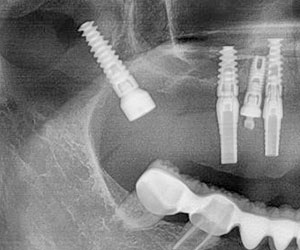

Rx panorámica postoperatorio inmediato de la colocación del implante pterigoideo

A los meses de espera de la osteointegración de los implantes, se procedió a la rehabilitación total de la cavidad oral, logrando devolverle a la paciente estabilidad, estética y función.